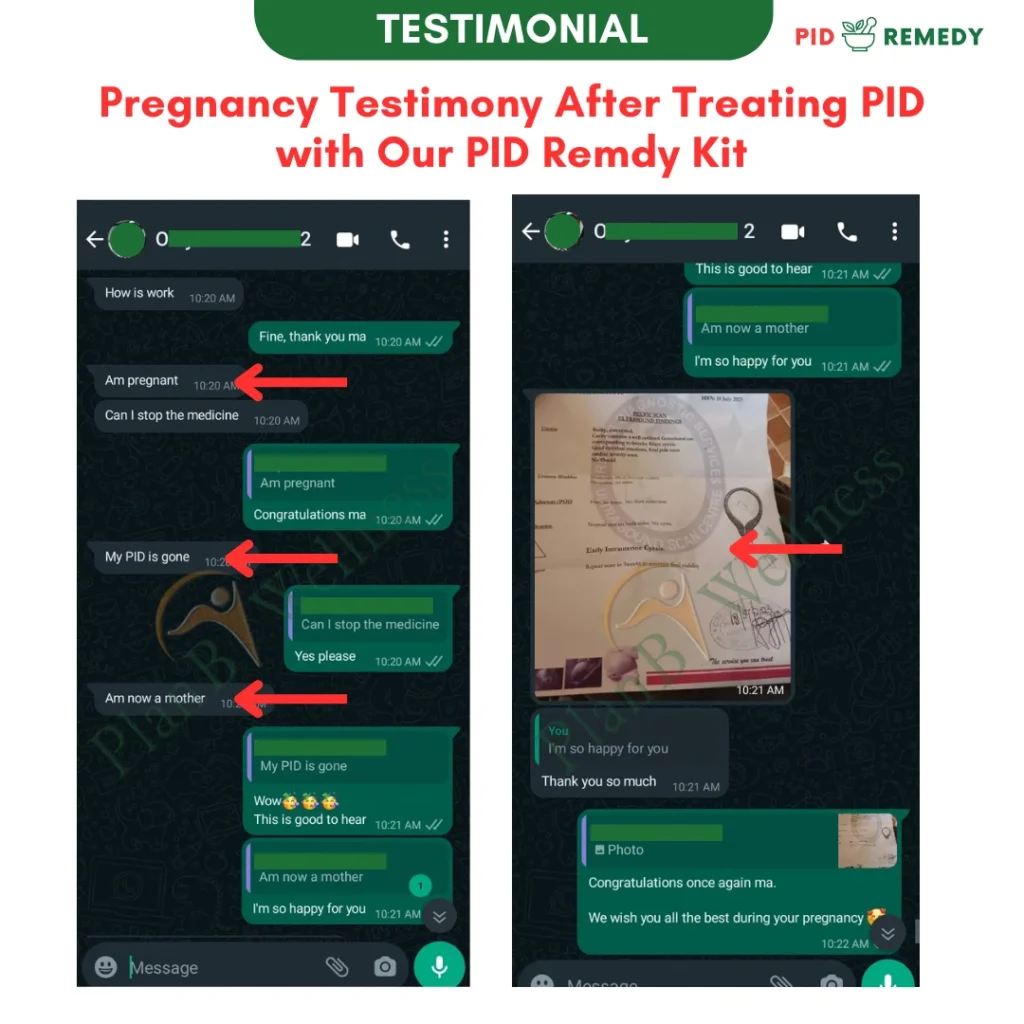

Our Happy Customers Who Love The PID Remedy Kit

Real Reviews From Real People

Our Happy Customers Who Love The PID Remedy Kit

Real Reviews From Real People

More Happy Customers

Real Reviews From Real People